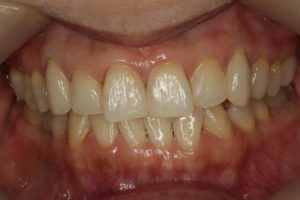

どのように変わったか、下の写真をご覧ください。

銀歯が多かったのですべて昔の銀歯の下もちりょうしながらセラミックにかえることができてとても満足しています。やっぱり白い歯よいですね。

治療お疲れ様でした。たくさん銀歯が入っていたのですが、最後には真っ白になりましたね。銀歯をやり直す材料にはセラミックとプラスティックがあるのですが、基本的にできるだけプラスティックで治すようにしています。この患者さんも、可能な限りプラスティックで治し、どうしても無理なところだけセラミックにしました。そのため歯を削る量が少ないことに加え、費用もかなり抑えることができます。たくさん治しましたが、全部セラミックで治さなければならないとなっていたら、もっともっと時間も費用もかかっていたかもしれません。当院では、初診時に治療方針や期間や費用などを1時間ほどかけて詳しく説明していますので、患者さんには治療内容について十分納得していただいていると考えています。「親身になって治療してくれる」とおっしゃっていただいたことは、そういったところを評価して頂いたのではいかと思っております。